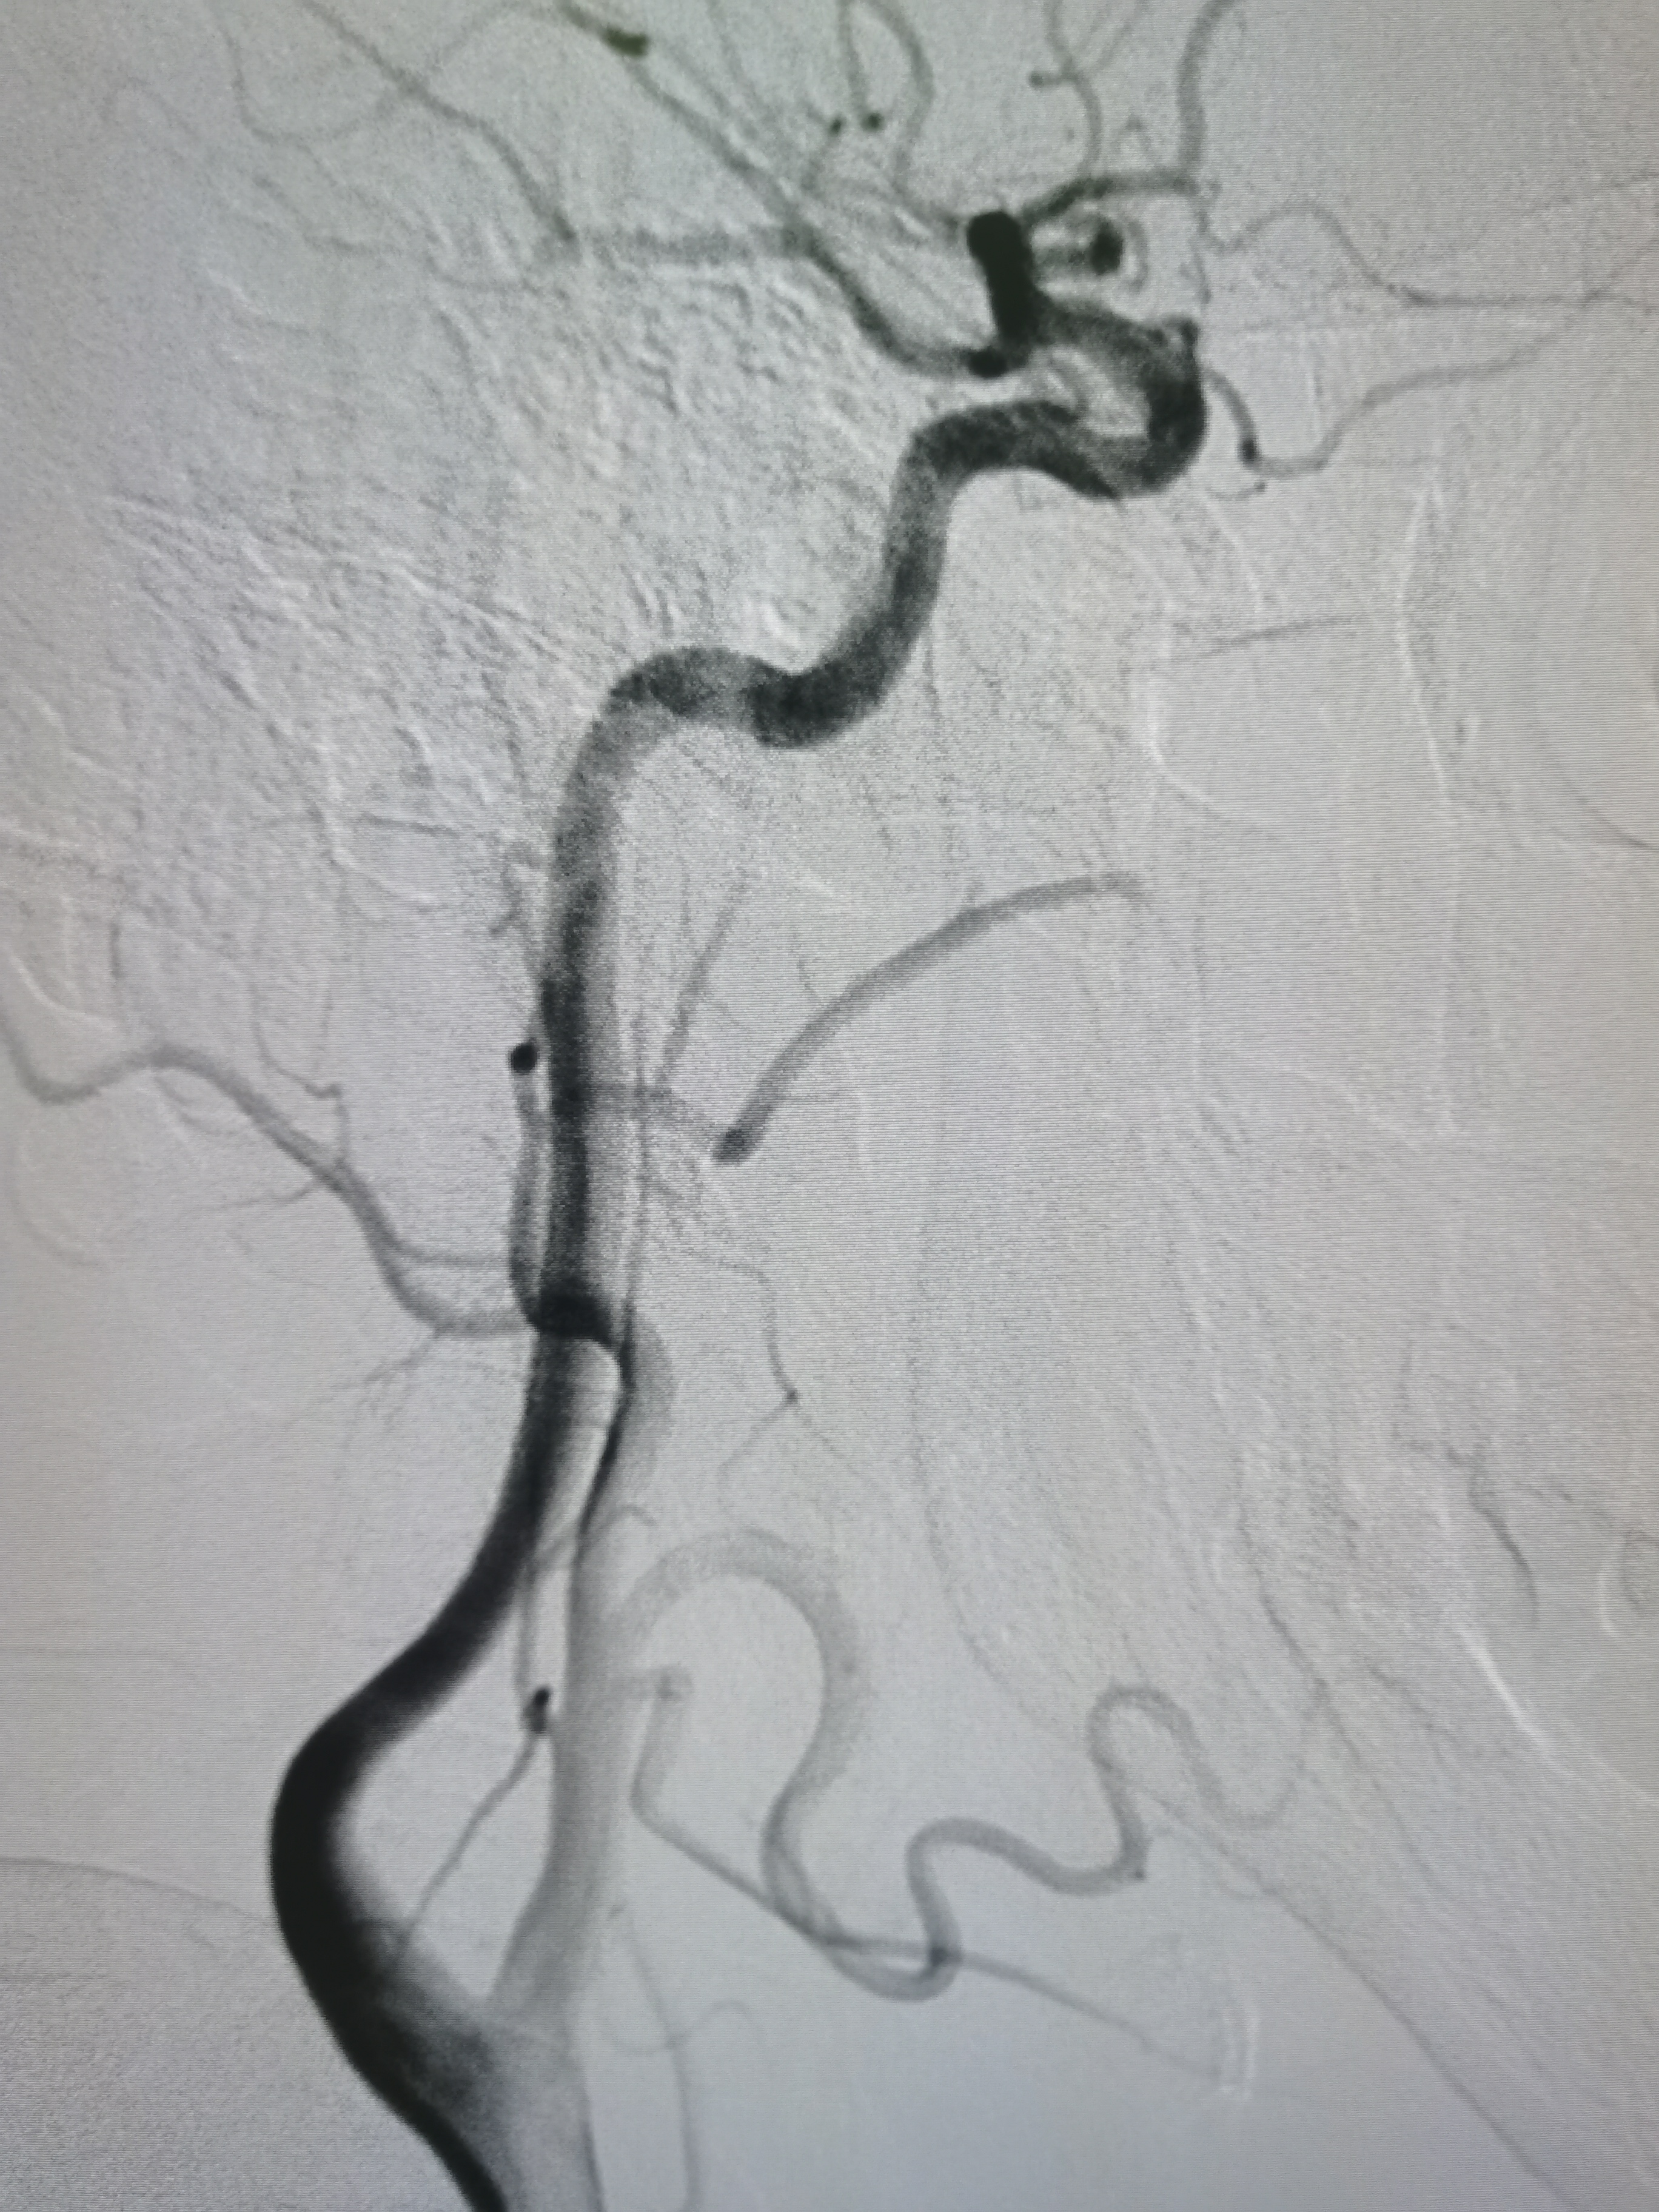

右侧颈内动脉正常。

右侧颈内动脉颅内段正常,胚胎型大脑后动脉。

左侧颈内动脉起始部正常。